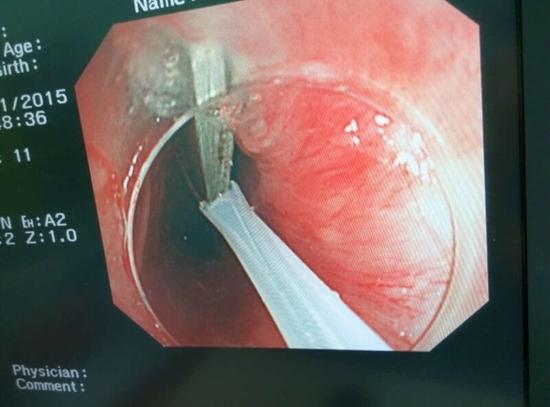

醫(yī)生從華先生胃里取出的鑷子和打火機

手術(shù)中,范醫(yī)生通過胃鏡準(zhǔn)確發(fā)現(xiàn)了胃里的鑷子。但讓他驚訝的是,在華先生胃底竟然還躺著三個被腐蝕了的打火機,打火機的金屬部件都已經(jīng)不見了。

隨后,范醫(yī)生先用圈套器套取出了長10厘米的鑷子,再一個一個地取出了打火機。整個取出過程小心謹(jǐn)慎而又一氣呵成,只用了不到10分鐘。